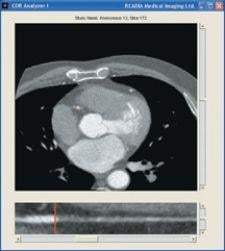

The COR Analyzer I by Rcadia Medical Imaging assists screening of triage patients for coronary artery disease. The computer-aided diagnostic software package uses proprietary image processing algorithms to analyze CT Angiography studies to provide fast and accurate identification of coronary artery disease (CAD).

To determine whether chest pain is caused by CAD, the system automatically reconstructs and accurately analyzes patient CTA images. In a recent pilot study, Rcadia COR Analyzer I successfully identified CAD in 100 percent of patients and 99 percent of the analyzed blood vessels.